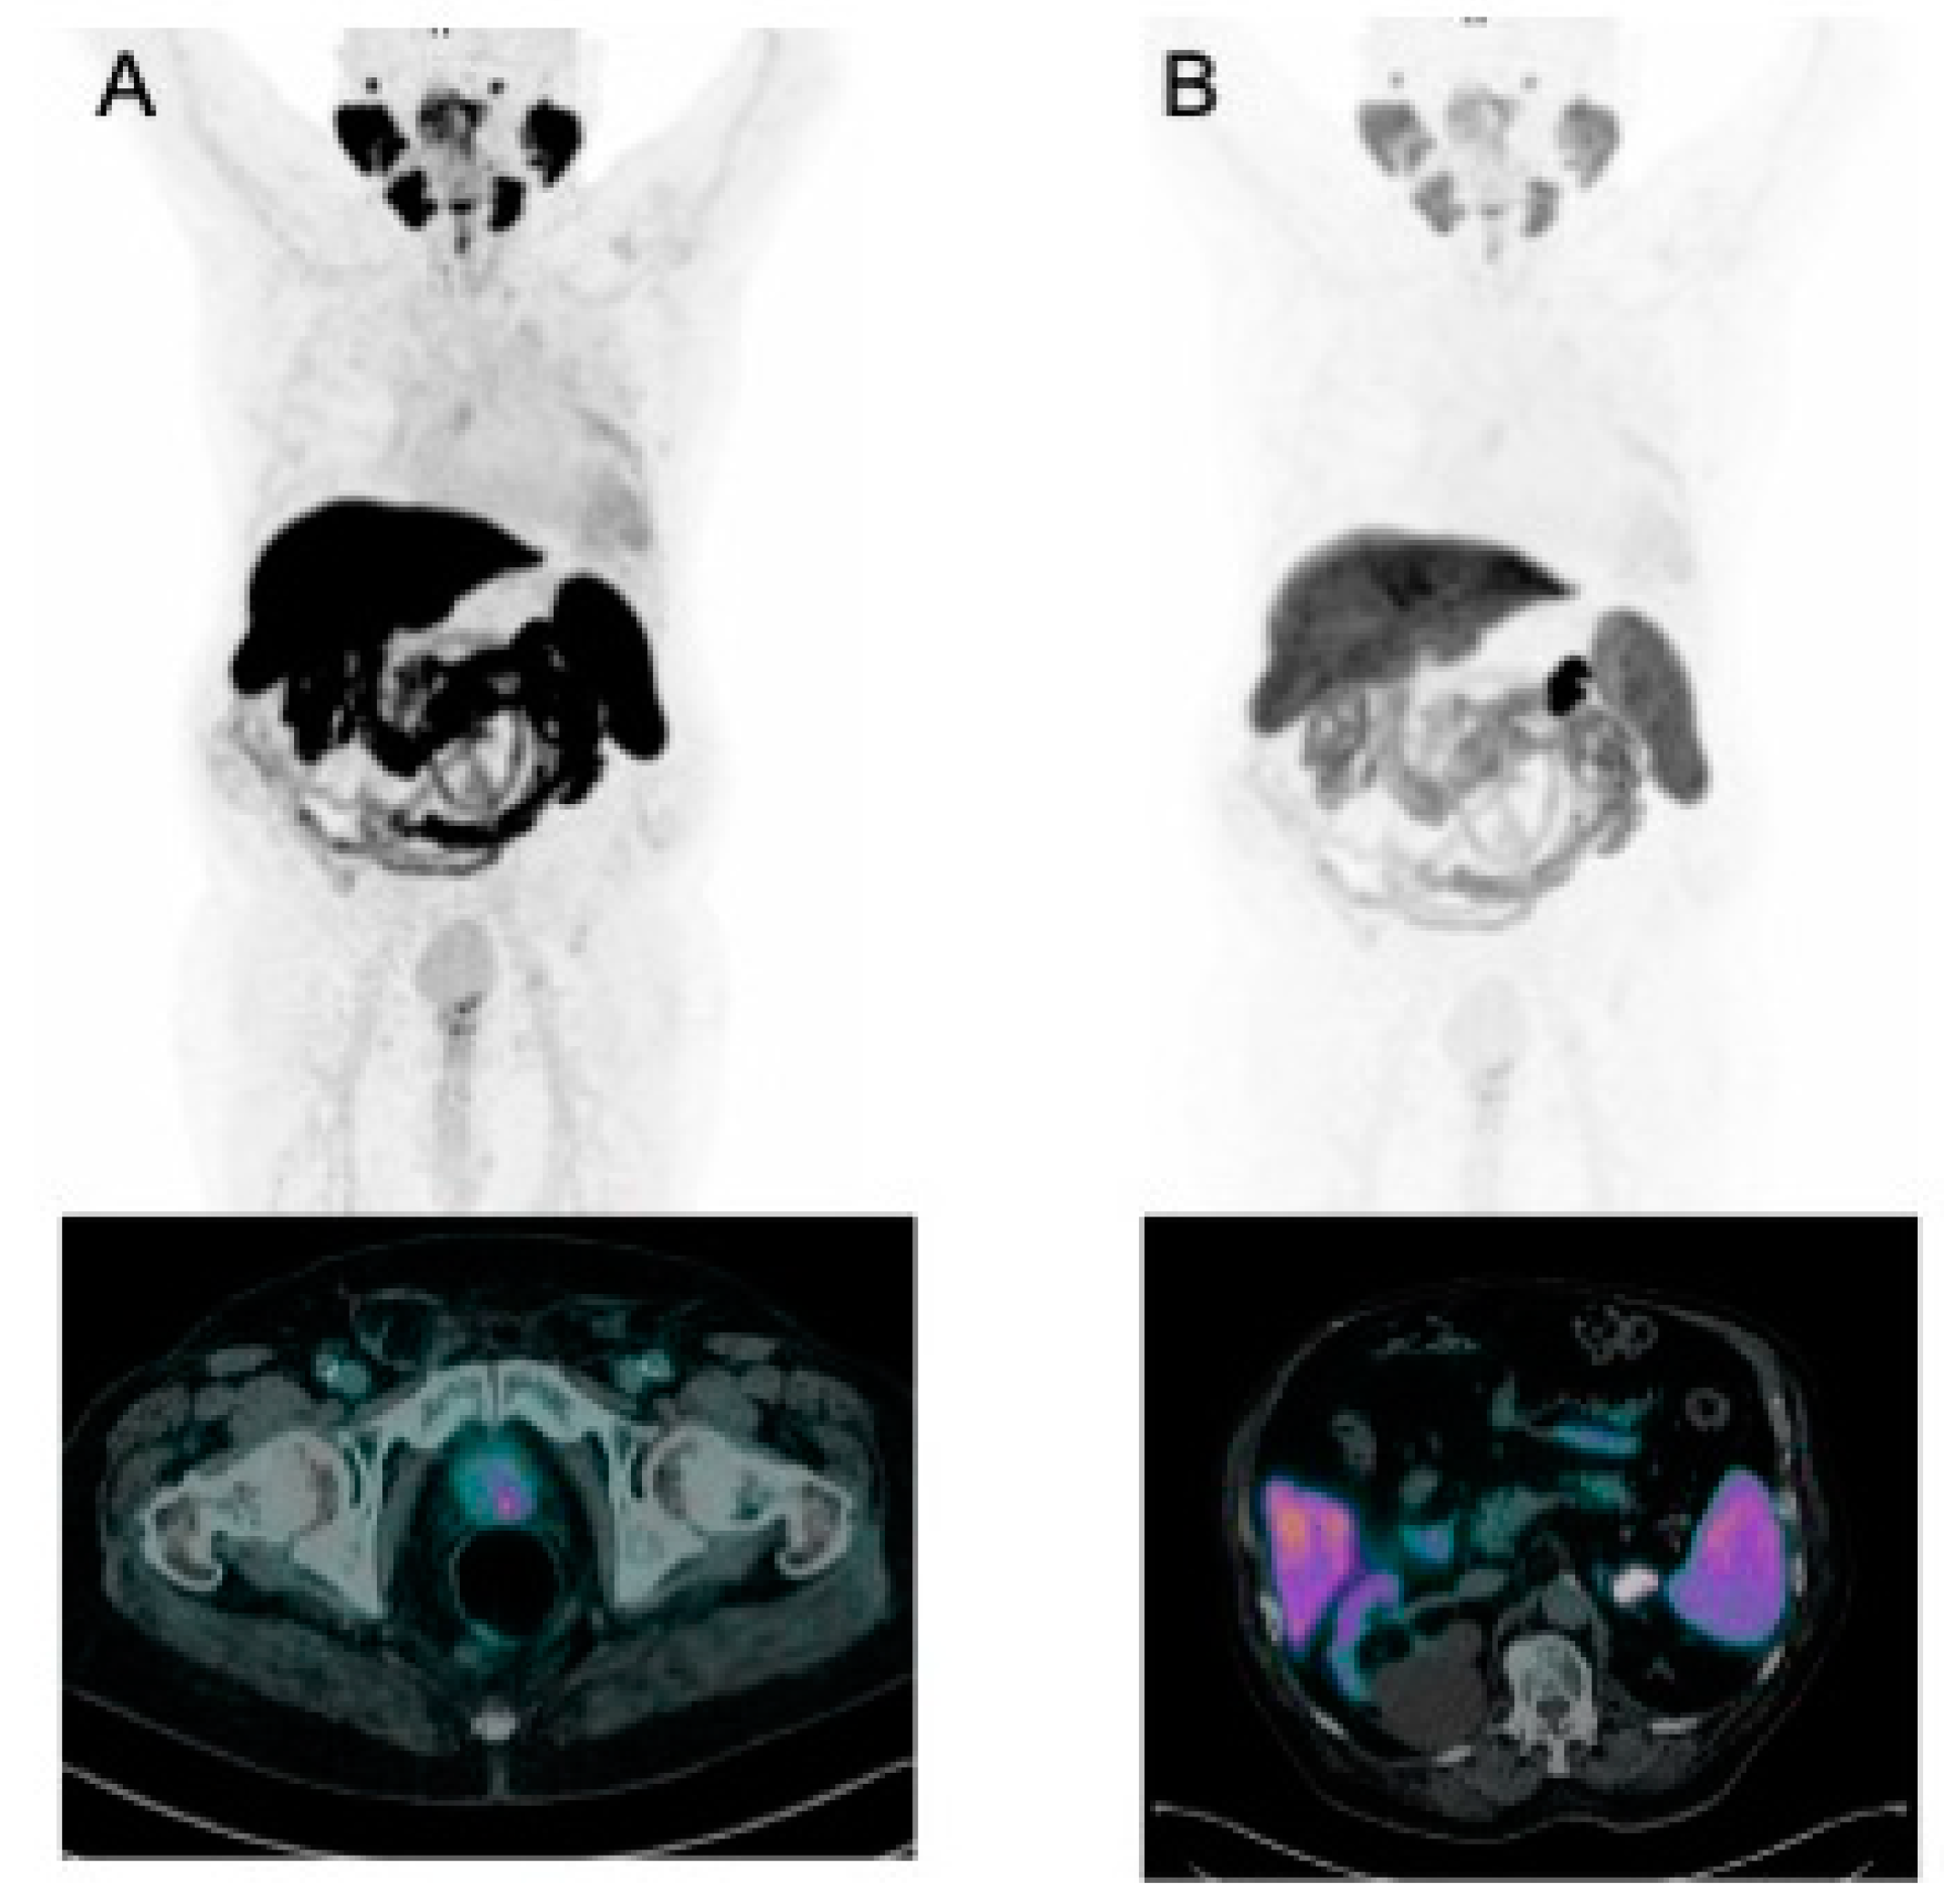

- Sivrikoz, I.A.; Deveci, H.; Ak, A.M.; Acer, E. 68Ga-PSMA PET/CT Images of Multiple Cutaneous Metastases in a Patient With Prostate Carcinoma: Complete Response to 177Lu-PSMA-617 Treatment. Clin. Nucl. Med. 2023, 48, 950–952. [Google Scholar] [CrossRef]